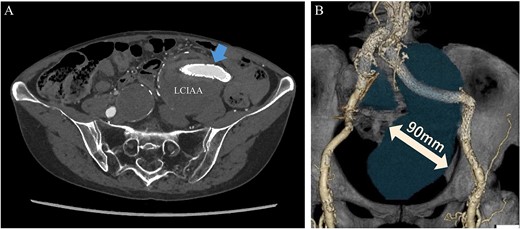

An 80-year-old female was admitted for the expansion of a left CIAA and IIAA. Ten years prior, she had undergone coiling of peripheral branches of the IIAA and stent graft placement in the CIAA. Contrast-enhanced CT showed the IIAA and CIAA extending into the deep pelvis. The maximum short diameter was 90 mm, and there were no signs of endoleak (Fig. 4).

Preoperative computed tomography imaging showing a left common iliac artery aneurysm and internal iliac artery aneurysm with a maximum short diameter of 90 mm. A—Axial image, B—3D image. LCIAA, left common iliac artery aneurysm.